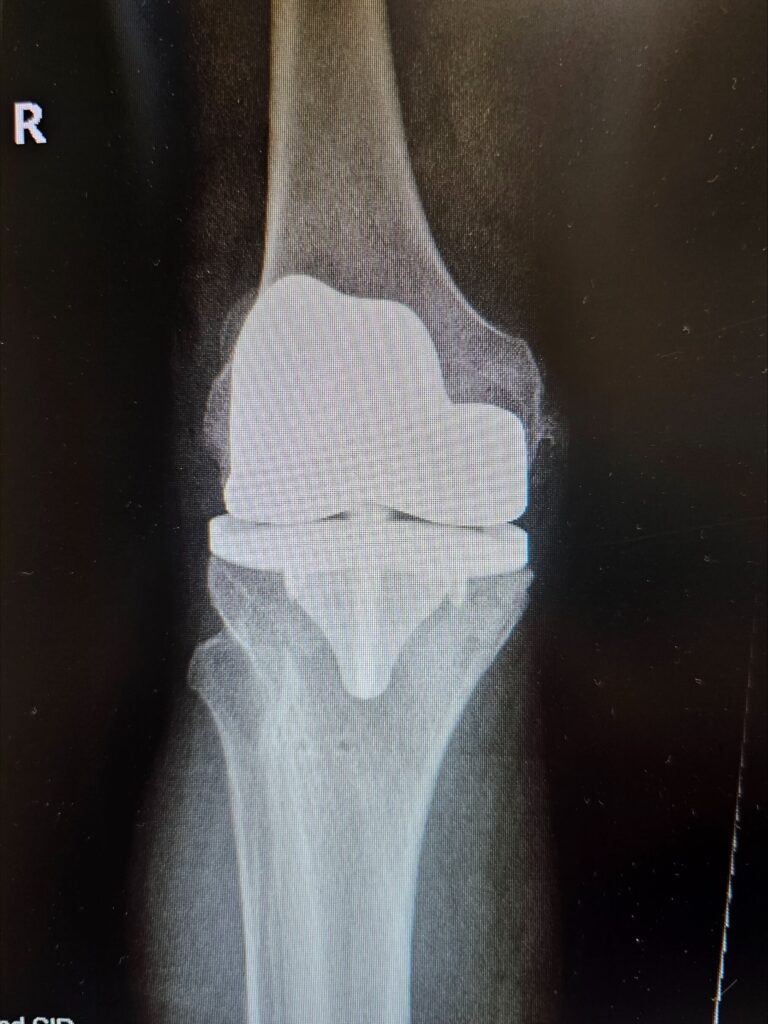

Last week marked a significant milestone in orthopedic surgery as Dr. Jared T. Lee, Medical Director and orthopedic surgeon at The Steadman Clinic in Aspen, Colorado, successfully performed the 5th ever customized press-fit total knee replacement in the United States — a monumental achievement that reflects his commitment to precision, innovation, and patient-centered care.

Traditional total knee replacements typically use standard implants fixed to bone with medical cement. In contrast, press-fit implants are designed to achieve stability through bone ingrowth — allowing the patient’s own bone to integrate with the implant surface over time rather than relying on cement fixation.

A customized press-fit knee goes even further: using advanced imaging (such as MRI or CT scans) taken before surgery, the implant is individually designed to match the exact anatomy of the patient’s knee joint. This tailored fit can improve alignment, preserve more bone, and maximize contact with the surrounding bone structure.

- Better fit, better function: Custom implants that match a patient’s unique anatomy can improve comfort, range of motion, and long-term function.

- Bone-preserving approach: Press-fit techniques can preserve more natural bone and may offer easier revision surgery if needed in the future.

- Next-generation innovation: Combining patient-specific design with press-fit fixation exemplifies how orthopedic technology is pushing toward individualized, long-lasting solutions.